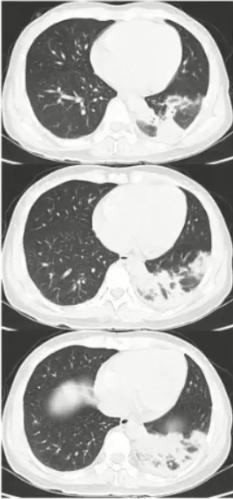

病例4

女性,40岁,既往体健。发热、咳嗽、咳黄痰12天入院。WBC:8.62G/L、N 84.1%,CRP 17.6 mg/dl

院外病原学检查结果:

痰涂片革兰氏阴性菌多量,痰培养肺炎克雷伯菌生长,院外肺炎支原体抗体1:40,呼吸道病原IgM九联检阴性。

院外治疗经过:

头孢曲松治疗3天,舒普深治疗4天,泰能治疗2天。

图4 患者肺部CT表现

病原学诊断和转归

病原学诊断:入院次日,肺炎支原体抗体1:640

转归:头孢曲松+左氧氟沙星治疗24小时后退热,治疗10天后出院

初始治疗失败的原因分析

• 混合感染:支原体感染的临床表现被细菌感染掩盖

• 缺乏肺炎支原体感染的早期临床技术